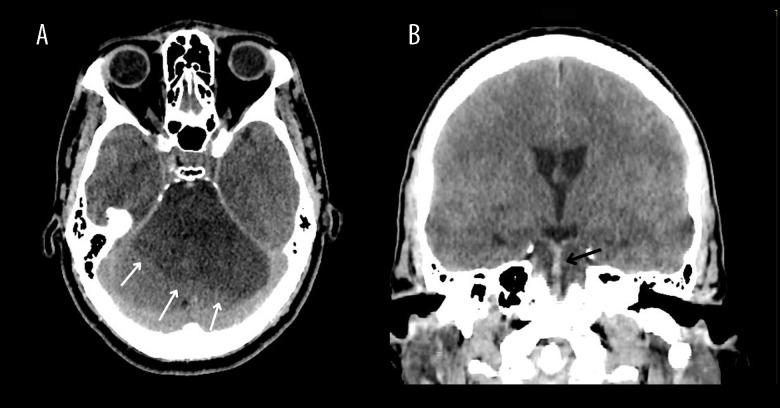

BACKGROUND Brugada syndrome is characterized by specific electrocardiographic changes predisposing individuals to ventricular arrhythmias and sudden cardiac death. Cases of coexisting Brugada syndrome and ischemic stroke are seldom documented, and an underlying pathophysiological link is yet unknown. This article presents a case in which a patient exhibited both Brugada syndrome patterns and an ischemic stroke, prompting a comprehensive literature review to explore the potential association between Brugada syndrome and ischemic stroke. CASE REPORT A 49-year-old man, previously healthy, was admitted to the hospital after being discovered unconscious at his workplace. Physical exam showed low oxygen saturation, fever, and abnormal neurological findings. Head computed tomography revealed a significant posterior circulation ischemic stroke. An electrocardiogram revealed Brugada syndrome type II initially, progressing to type III pattern. Despite efforts, the patient's condition rapidly deteriorated, leading to death within 24 hours. As far as we're aware, Brugada patterns following a posterior circulation ischemic stroke have only been documented in 1 other instance, in which the patient was also diagnosed with atrial fibrillation. CONCLUSIONS Both our literature review and the presented case indicate that Brugada patterns may coexist with and even be associated with ischemic stroke. More extensive research is required to shed light on this potential association. The question of whether Brugada syndrome is a precursor to or a result of ischemic stroke remains unanswered. We propose that patients with ischemic stroke should undergo an evaluation for electrocardiographic signs indicative of Brugada syndrome, particularly if no clear causes, like cardioembolism, are evident.